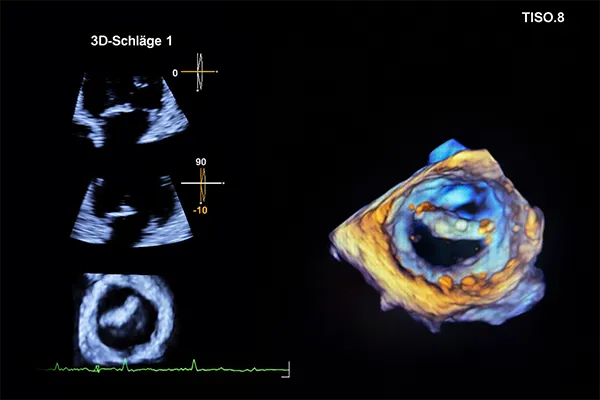

In unserer spezialisierten ambulanten Klappensprechstunde bieten wir Ihnen eine umfassende, unabhängige und leitliniengerechte Abklärung von Herzklappenerkrankungen. Im Mittelpunkt stehen eine präzise Diagnostik, ausreichend Zeit für Gespräche und eine gemeinsame, informierte Entscheidungsfindung.

Diagnostische Verfahren in unserer Klappstunden

Erweiterte Diagnostik und weitere Verfahren der ambulanten Klappensprechstunde

Je nach individueller Fragestellung stehen uns weitere diagnostische Verfahren zur Verfügung:

- Spiroergometrie: Objektivierung der Leistungsfähigkeit

- Stressechokardiographie: Ultraschall des Herzens unter Belastung zur Beurteilung des Schweregrades eines Klappenfehlers